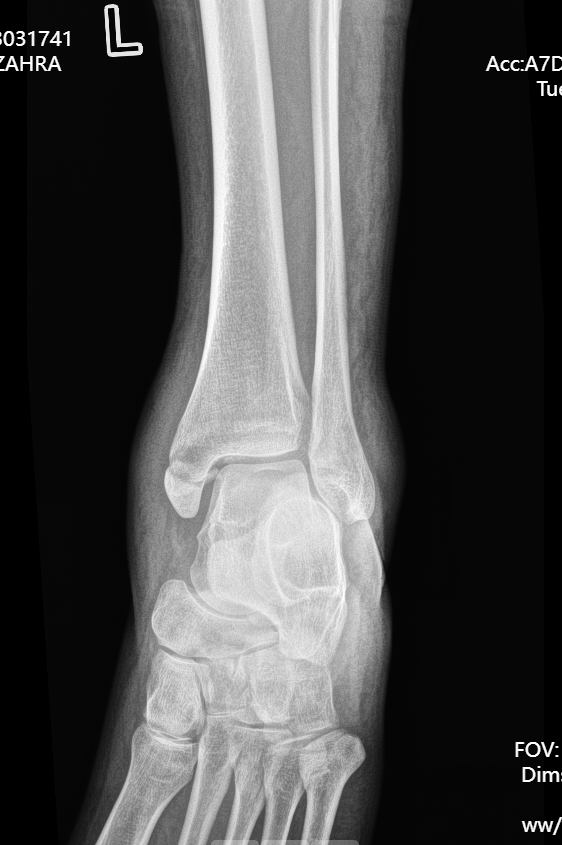

患者因意外受伤后踝关节疼痛、肿胀、无法行走,急诊就诊于成人ai 。

经检查确诊为旋前外旋 Ⅳ 度踝关节骨折,包含腓骨中段骨折、内踝骨折、后踝骨折及下胫腓联合分离,属于临床中结构复杂、稳定性破坏较严重的踝关节损伤。